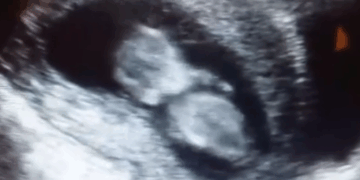

The Tennessee General Assembly has passed legislation that would hold out-of-state distributors of abortion pills accountable when the drugs are mailed into the state and result in the death of a preborn child. The goal of the bill is to stop…